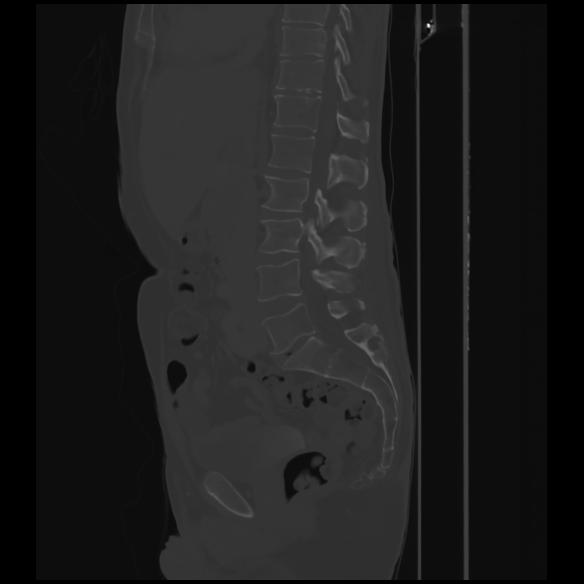

7 CUERPO,CE,Sagittal,3.000,CUERPO,Sagittal,